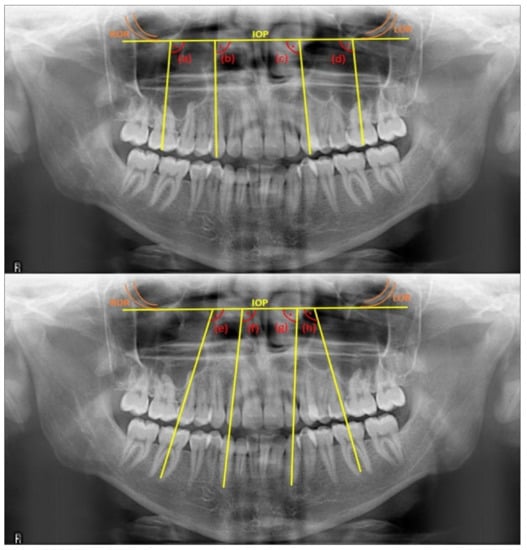

The measurements in panoramic radiographs were performed using the IC Measure program (for Windows, version 2.0.0.286, The Imaging Source, LLC, Charlotte, NC, USA). The interorbital plane, which extended between the most inferior points of the right and left orbital rims, was constructed as a reference [26]. Mesiodistal axial angulation angles were measured for canines as follows: the angle between the interorbital plane and the line parallel to the long axis, combining the incisal edge and root apex, while for the first molars, it was the angle between the interorbital plane and the parallel line to the long axis, which divides the crown into two equal parts as mesiodistal [26] (see Figure 1). Measurements were performed blindly by the researcher (O.C.), according to the sequence identification number given to each sample, regardless of the groups [3].

Figure 1. Mesiodistal axial angulation angles measured in the study: (a) for tooth 16, (b) for tooth 13, (c) for tooth 23, (d) for tooth 26, (e) for tooth 46, (f) for tooth 43, (g) for tooth 33, and (h) for tooth 36. ROR: right orbital rim; LOR: left orbital rim; IOP: interorbital plane.